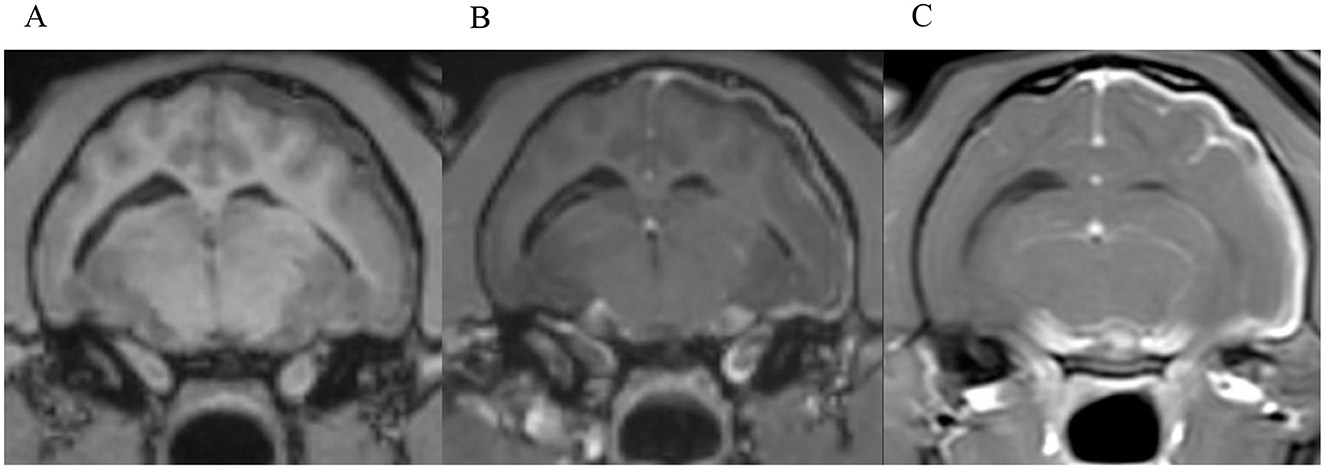

3.7 Additional observations

Two observers noted potential alternative routes of intracranial extension of disease besides the internal acoustic meatus. This was corroborated by the first and last authors in consensus. There was a total of 18 cases where inflammation appeared to extend through the jugular foramen (Figure 10). In 11 cases, the pathway of intracranial extension was suspected to be the oval foramen and in 5 cases both of the aforementioned routes were suspected to be involved. The identification of these presumed alternative routes was exclusively based on MRI findings such as the pattern of contrast enhancement, but no histopathological confirmation is available.

Figure 10. Transverse T1W-TSE post-contrast SPIR image at the level of the right jugular foramen. Example image of a dog with a presumed alternative route of intracranial extension through the right jugular foramen with regional meningeal enhancement. Note the marked contrast enhancement of the tissues around the right tympanic bulla (the right side of the image is the left side of the patient).